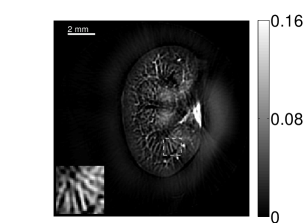

VI-E Results: kidney phantom

The images and EIRs reconstructed by use of the VP algorithm that was based on the 2D imaging model that neglected the SIR are shown in Figures 15 and 16. The latter figure contains results corresponding to different values for the regularization parameter . From Fig. 15, it can be observed that use of the conventional iterative method that utilized the measured EIR resulted in distortions and loss of details in the reconstructed images. Use of the VP algorithm improved the contrast and the details in the reconstructed images (Fig. 15(c) and 16(a)). Furthermore, the images reconstructed by use of the VP algorithm had a more uniform background.

In Figure 17, the results corresponding to use of the 3D imaging model that incorporated SIR effects are shown. The EIR estimated by the VP algorithm is also shown. In Figure 18, images and EIRs reconstructed by use of the VP algorithm with different regularization parameters values are shown.

Similar to the case described above where the transducer SIR was neglected, these results reveal that use of the VP algorithm can produce images with a cleaner background and enhanced spatial resolution than yielded by use of a conventional iterative algorithm that employed the measured EIR. For example, detailed information regarding the vessels near the organ’s periphery was better preserved by the VP algorithm than by the conventional iterative algorithm. These images corroborate our assertion that the VP algorithm can significantly reduce the artifacts and distortions in the reconstructed image. It is also worth pointing out that, unlike the numerical phantom studies, the artifacts and distortions in the images may be caused not only by the inaccurate EIR but also by other factors, such as neglecting acoustic heterogeneities and the variation of the EIRs among the elements of the transducer array. In such cases, the EIR estimated by the VP algorithm represents an effective system impulse response that minimizes the inconsistency between the measured data and the imaging model.